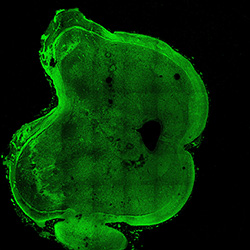

An in vivo and in vitro spatiotemporal profile of human midbrain development

An anatomical analysis of the developing human midbrain from 6 post-conceptional weeks (PCW) to 22 PCW reveals increased tissue complexity, characterized by the emergence of dopaminergic nuclei, as highlighted by immunofluorescence analysis for tyrosine hydroxylase (TH).

6PCW human midbrain